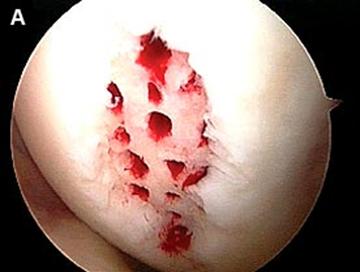

Fig.22. Debridarea (a, b, c).

a. b.

Fig.25.a. Debridarea. Fig.25.b. Microfracturare.